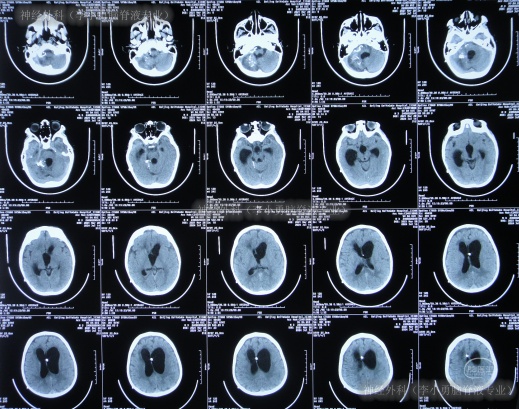

入院后10天即2024年6月12日,查头颅CT示脑室有所缩小(图-9)。

图-9:2024年6月12日头颅CT

入院后12天即2024年6月14日,头颅CT示脑室进一步缩小(图-10);意识变得完全清楚能喊爸爸妈妈,能回答(图-11)。

图-10:2024年6月14日头颅CT